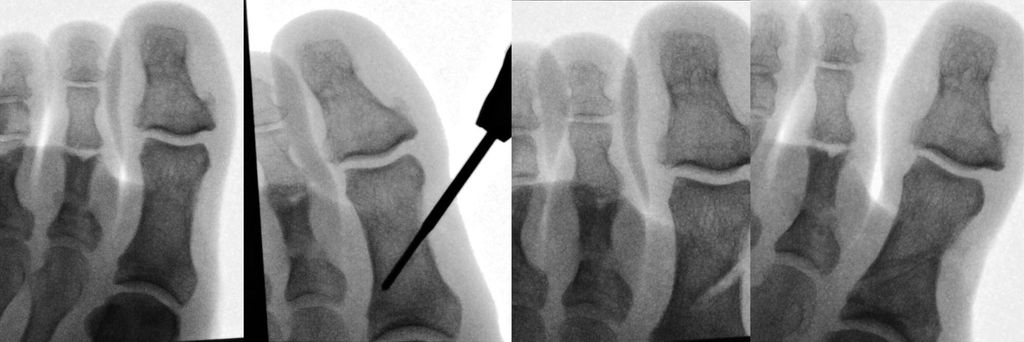

Auch die Akin-Osteotomie kann sehr einfach minimalinvasiv durchgeführt werden. Sie wird entweder mit einer Schraube oder aber einfach mit Tapes für 4 Wochen stabilisiert (Abb. 2).

Minimalinvasive Cheilektomie

Unter entsprechender Lagerung mit Bildwandler erfolgt ein 1cm langer Hautschnitt dorsomedial ca. 3 cm proximal des Gelenkspaltes. Eventuell ist noch ein zweiter dorsolateraler Hautschnitt notwendig. Mit einem Raspatorium wird die Gelenkkapsel vom Knochen abgehoben. Der Osteophyt wird mit der Shannon-Fräse abgetragen. Knochenfragmente werden mit der Klemme entfernt und das Knochendebris wird ausgespült (Abb. 3).

Teoh et al.präsentierten 89 Patienten mit 98 behandelten Füßen.9 Die Schwellung hielt im Schnitt für 5,3 Wochen an. Der VAS wurde im Schnitt von 8,0 auf 3,0 verbessert. 12 Patienten wurden revidiert und bei 7 davon wurde auf eine Arthrodese gewechselt. Es gab 2 Wundinfekte und 2 Wundheilungsstörungen. Sidon10 und Glenn11 zeigten ähnlich positive Ergebnisse.